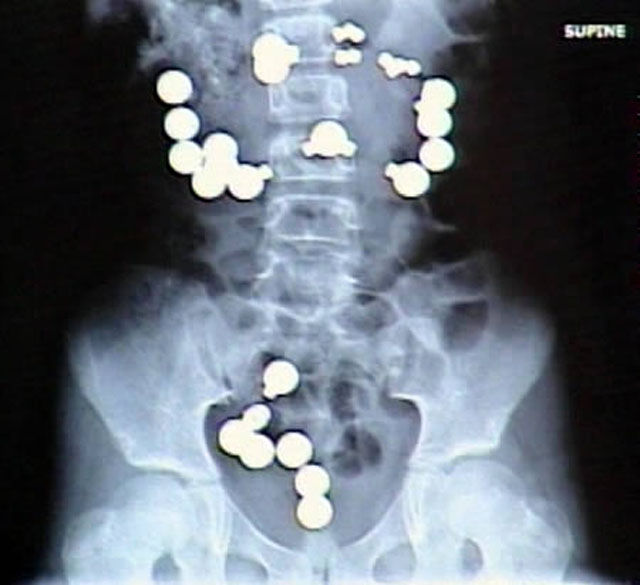

8-year-old Haley Lents of Indiana swallowed 10 magnets and 20 steel balls from a Magnetix toy set. The magnets and balls attracted one another within her digestive tract, ripping a total of eight holes in her intestines and forcing her parents to rush her to the hospital for emergency surgery. Lents later told reporters that the magnets and steel balls "looked like candy"

52-year-old Dutchwoman Margaret Daalman came to hospital complaining of stomach ache, and one glance at her X-ray shows why.Surgeons in Rotterdam in the Netherlands were astonished when X-rays showed 78 different items of cutlery in her stomach.